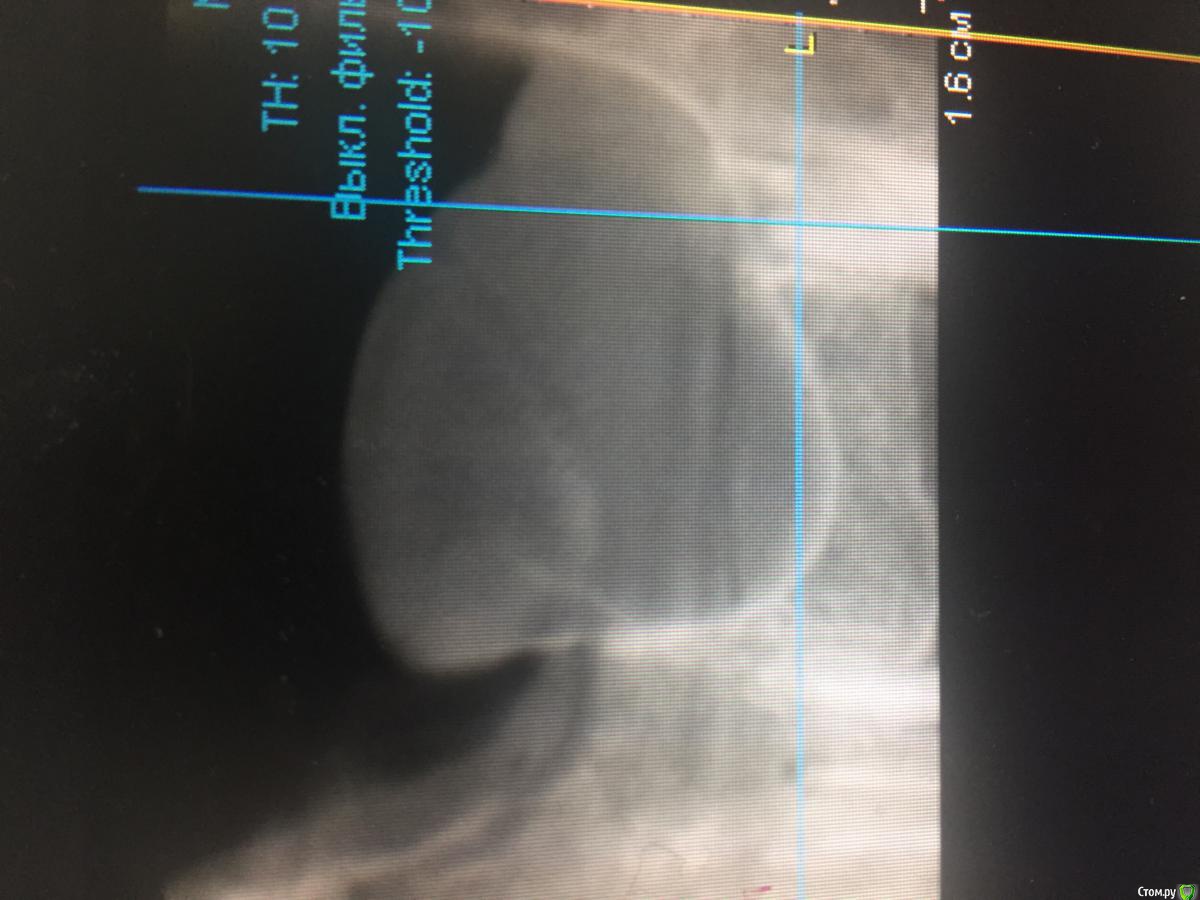

Большой Зеленый Опубликовано 27 октября, 2016 Поделиться Опубликовано 27 октября, 2016 Можно просто удалить зуб и подождать.http://s016.radikal.ru/i337/1610/a7/312926353b71.png После удаления через 4 месяца все исчезло само собой.http://s020.radikal.ru/i720/1610/31/06bf3c384fa8.jpg 3 Ссылка на комментарий

Makskras Опубликовано 27 октября, 2016 Поделиться Опубликовано 27 октября, 2016 В первом клин. случае - ретенционная киста (простят меня гистологи). я бы сначала удалил 28, потом опорожнил и удалил кисту (либо просто опорожнил) . А во втором -скрее всего просто гипертрофия слизистой (реакция на хр Pt) , поэтому и прошла сама собой после удаления причины. Ссылка на комментарий

Карен Аванесов Опубликовано 27 октября, 2016 Поделиться Опубликовано 27 октября, 2016 Андрей, да, после удаления картина станет лучше, но если есть киста она не исчезнет, ты то умело обошел пазуху, а в представленном случае синус неизбежен. 1 Ссылка на комментарий